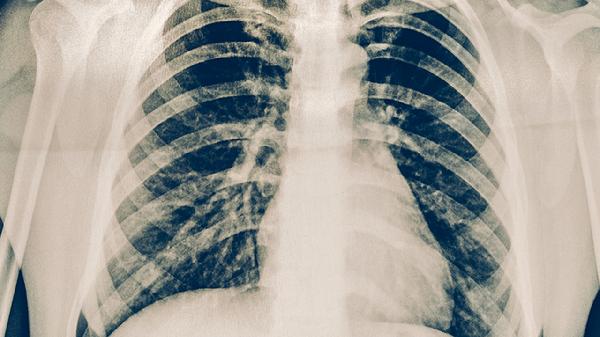

3、影像学特征

肺结核在胸片上多表现为上叶尖后段或下叶背段的浸润性病变,可伴有空洞形成。肺癌在影像学上多表现为孤立性结节或肿块,边缘不规则,可能伴有毛刺征、分叶征等恶性征象。